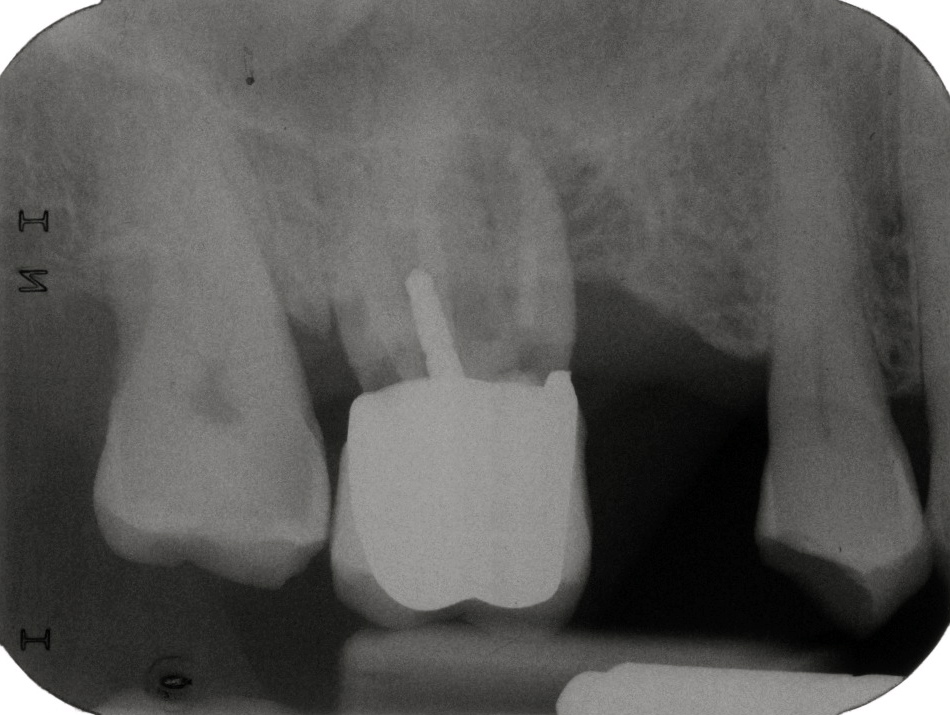

Der nächste Stift

von Bodald Necker

Nachdem die letzte Woche mit einem Stift endete, geht diese Woche mit einem Stift los.

Der Patient wurde zur Endo an 26 überwiesen. Nachdem diese abgeschlossen war, stand er 14 Tage später mit einer abgebrochenen Krone an 12 da.

Der Zahn war anderenorts wurzelbehandelt, und vor der Kronenversorgung mit einem geschraubten Stahlstift versorgt worden. Der Bruch verlief ziemlich genau entlang des Kronenrandes, der Stahlstift brach ca. 2 mm tiefer.

Um den Zahn zu erhalten und mit einer neuen Krone verzogen zu können musste das im Wurzelkanal verbliebene Fragment des Stiftes, entfernt werden. Eine anschliessende komplette Revision der Wurzelfüllung bot sich an.

Zur Stiftentfernung:

Der Rest des Stiftes saß fest in der Wurzel, es war kein Riss im Dentin zu erkennen, welcher den Verdacht einer Längsfraktur aufwarf. Karies war auch nicht zu erkennen.

Die Entfernung erfolgte mit Ultraschall. Es wurden verschiedene Spitzen verwendet, als effektivste Spitze erwies sich bei mir wieder die NSK E5 Spitze.

Diese ist im Urzustand an der Spitze plan, da sie für laterale Kondensation gedacht ist. Da dies im Schlumbohm US meine Standard-Spül-Spitze ist, und die Kante an der vorderen Planfläche leicht Scharten in die Kanalwand schlägt, wird die Kante an der Spitze mit einem Arkansas-Stein gebrochen.

Wenn die Spitze benötigt wird, um Dentin ab zu tragen, kann man sie auch anspitzen. Entweder mit einem Arkansas-Stein im Winkelstück oder man geht mit aktivierter Spitze über einen Zurichtstein.

Mit einer scharfen Spitze ist der Dentinabtrag deutlich höher. Da aber leider das US-Handstück vom Schlumbohm Copilot vom Hersteller aus (noch) nicht auf volle Leistung programmiert ist (ich hoffe im nächsten Update ist es verbessert!), bin ich nach kurzer Zeit umgestiegen auf mein „gutes, altes“ Satelec P5 boost.

Mit der gespitzten Spitze wurde Dentin zirkulär um den Stift abgetragen, bis dieser sich löste. Anschließend apikal vom Stift die Zementreste entfernt bis die Wurzelfüllung frei lag, diese wurde entfernt, der Kanal erweitert mit EDTA, NaOCl gespült mit Calciumhydroxid versorgt, provisorisch verschlossen, ein Provisorium angefertigt und der Patient entlassen.

WF und die prophetische Versorgung folgen.

1 / 7